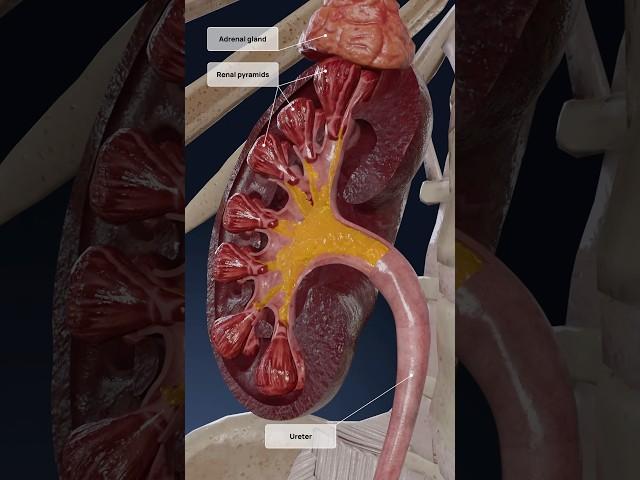

Работа почек, 3D объяснение: образование мочи

Работа почек, 3D объяснение: образование мочи

VOKA 3D Anatomy & Pathology | Rus